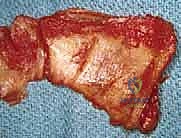

في حالات التمزقات الضخمة، قد تكون الأوتار متراجعة وملاصقة للعظم ومغطاة بالتليفات. هنا تبرز أهمية الجراحة المفتوحة، حيث يتم تحرير الأوتار بعناية فائقة وإعادتها إلى مرونتها الطبيعية لتصل إلى مكان تثبيتها الأصلي دون شد مفرط.

المرحلة الثالثة: زراعة الخطاطيف وخياطة الأوتار

يتم تحضير "بصمة الوتر" (Footprint) على رأس عظم العضد عن طريق تقشير العظم بلطف لتعزيز النزيف الخفيف الذي يجلب الخلايا الجذعية وعوامل النمو لتسريع التئام الوتر بالعظم.